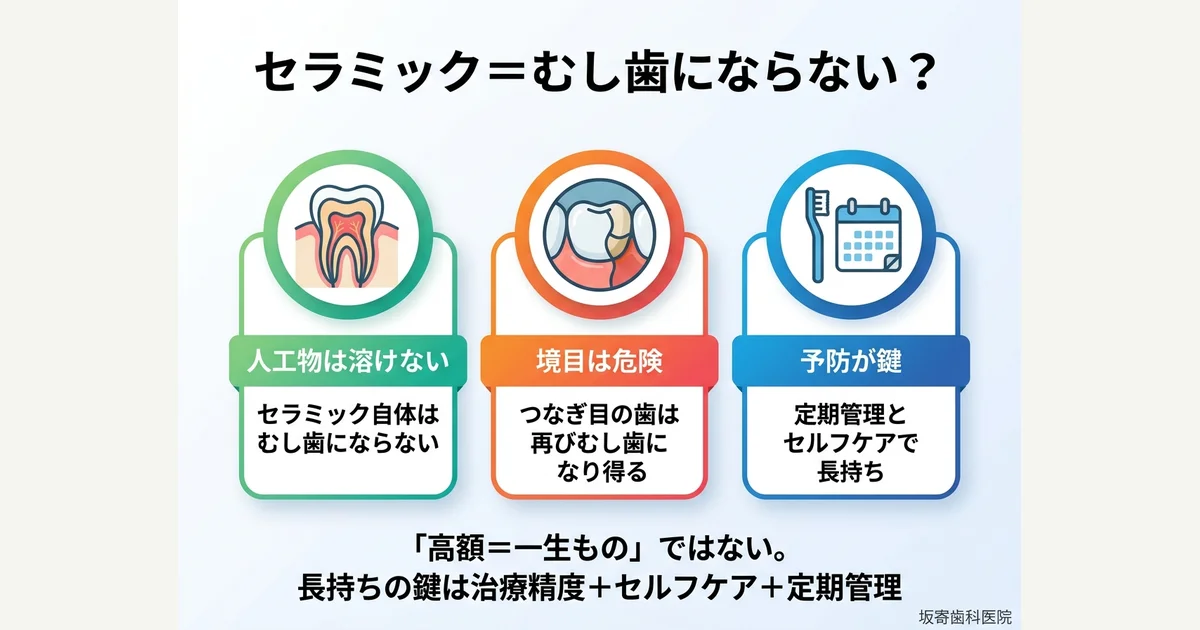

「セラミックはむし歯にならない」は本当?歯科医師がエビデンスで解説

セラミック修復でもつなぎ目の歯は二次う蝕になり得ます。11本の論文に基づき、長期生存率・失敗原因・長持ちの条件を歯科医師が解説。